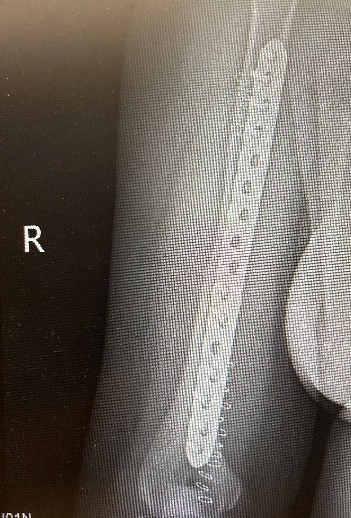

10月5日,40岁李先生摔倒致右肩部着地,8:40入院后,高峰医师团队诊断为“右肱骨近端粉碎性骨折”,13:35做好充分术前准备后历经3小时手术完成。